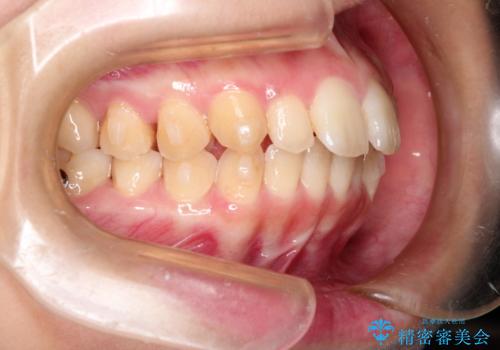

出ている前歯をインビザラインにて引っ込める

- 前歯が少し前に出ているのが気になるとのことで来院されました。

インビザラインにて上顎の歯を全体的に後方に移動させて前歯を引っ込める計画としました。

使用時間を守っていただけたので、比較的スムーズに矯正を終了することができました。